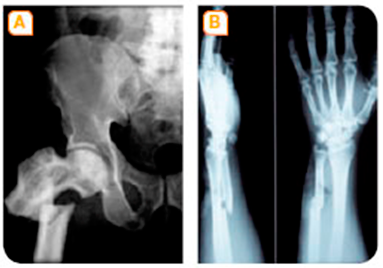

Al nostre cos tenim tres tipus d’ossos diferents: plans, llargs i curts.

Quan som bebés, quasi tot l’os és cartílag. A mesura que anem creixent, el cartílag de l’esquelet es reforça amb sals minerals i es converteix en os. Aquest procés es diu ossificació i acaba cap als 18 anys en els homes i aproximadament als 16 en les dones.